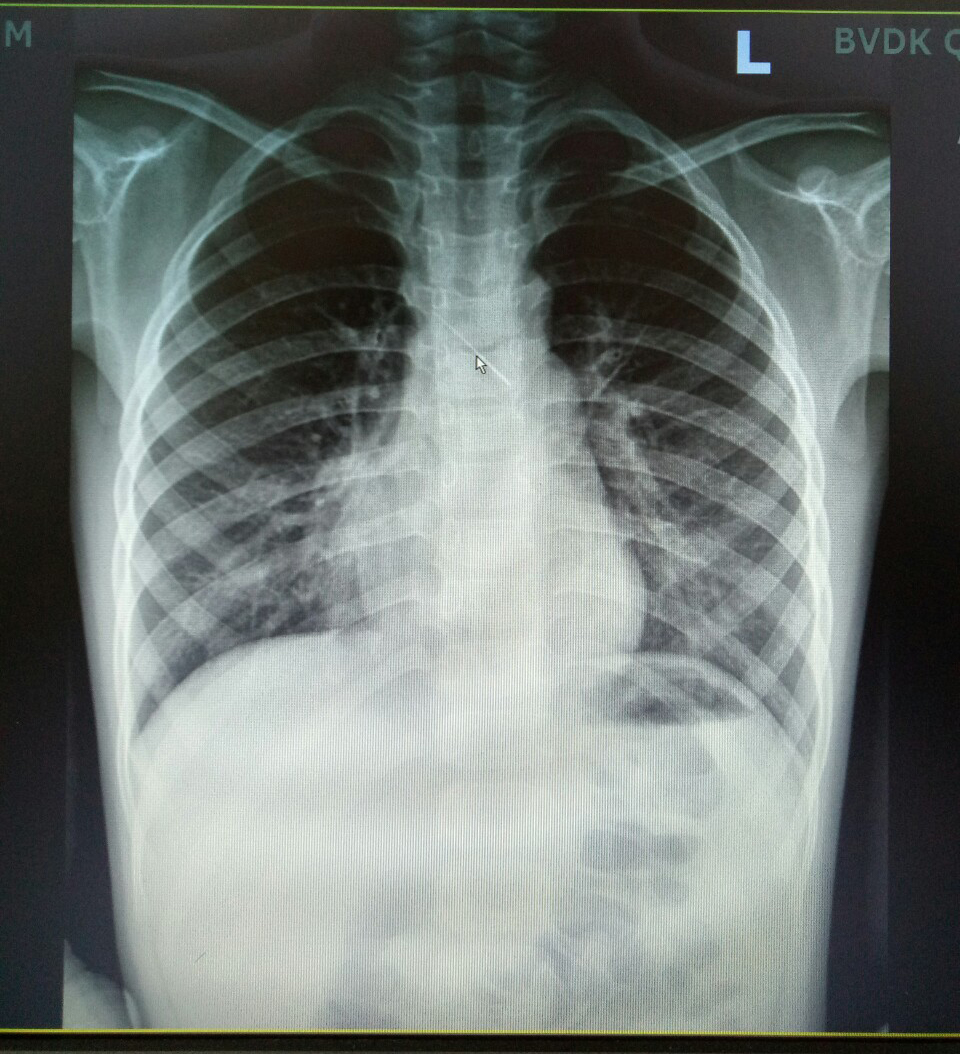

Viêm phổi do Mycoplasma pneumoniae (MP) là gì? Những điều cần biết về viêm phổi do Mycoplasma pneumoniae